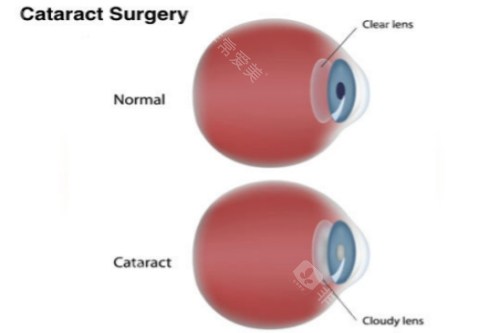

基于第七次国境内人口普查数据,呼市常住人口344.61万人,65岁以上老年群体占比达13.83%,总量约50万人。而中华医学组织眼科学分会的统计显示,我国60岁以上人群白内障发病率约80%,庞大的患病基数让政策延续成为民生刚需。

医学层面,申请者需经专科诊断确诊为白内障,且裸眼视力≤0.3或矫正视力<0.5,这一标准是判断手术必要性的核心依据。同时需排除相关禁忌症,例如活动性眼部感染、未控制的全身性疾病等。